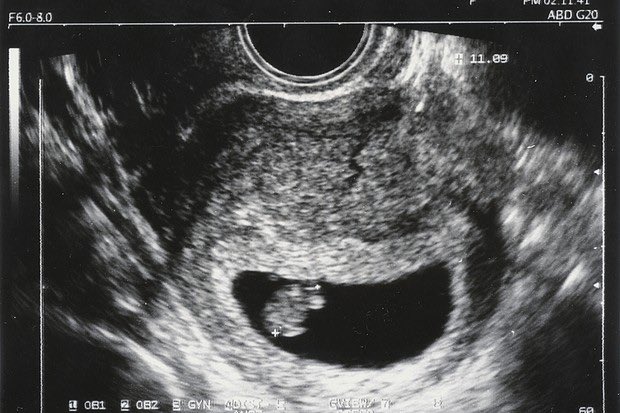

٩- بعد اسبوعين من ترجيع الاجنة يتم عمل تحليل الدم الرقمي لمعرفة حدوث الحمل واذا كان ايجابيا يتم تكراره مرتين لمعرفة ارتفاع مستواه وبعد أسبوعين من التحليل الايجابي أي ٤ أسابيع من تاريخ إرجاع الأجنة يتم عمل الاشعة الصوتية لمعرفة مكان الحمل وعدد اكياس الحمل ونبض الجنين..